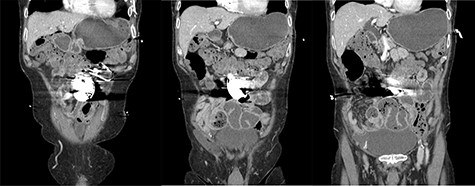

A presentation 6 weeks later was once again diagnosed as ASBO, with multiple segments of dilated small bowel with a transition point identified in the right iliac fossa on CT scan (Figs 1 and 2). On this occasion, operative management was required, with the AICD identified to the left of the umbilicis with extensive matted adhesions to small bowel encountered. Extensive adhesiolysis was undertaken at this area, with the defibrillator removed from the intra-abdominal cavity and repositioned in a subrectus pocket. Following the procedure, the AICD was reactivated and confirmed to be operating as expected. The patient responded well to operative management and began opening his bowels on the third day postoperatively. The patient tolerated a diet and was able to be discharged home. He was reviewed in the clinic 6 weeks after the laparotomy, and at this time it was found he had continued to open his bowels regularly and was undertaking his usual activities with nil issues. The patient had not had any further episodes or symptoms concerning for obstruction.

Coronal slices of computed tomography scan shown beam hardening artefact from intra-abdominal AICD, adjacent to distended loops of small bowel.